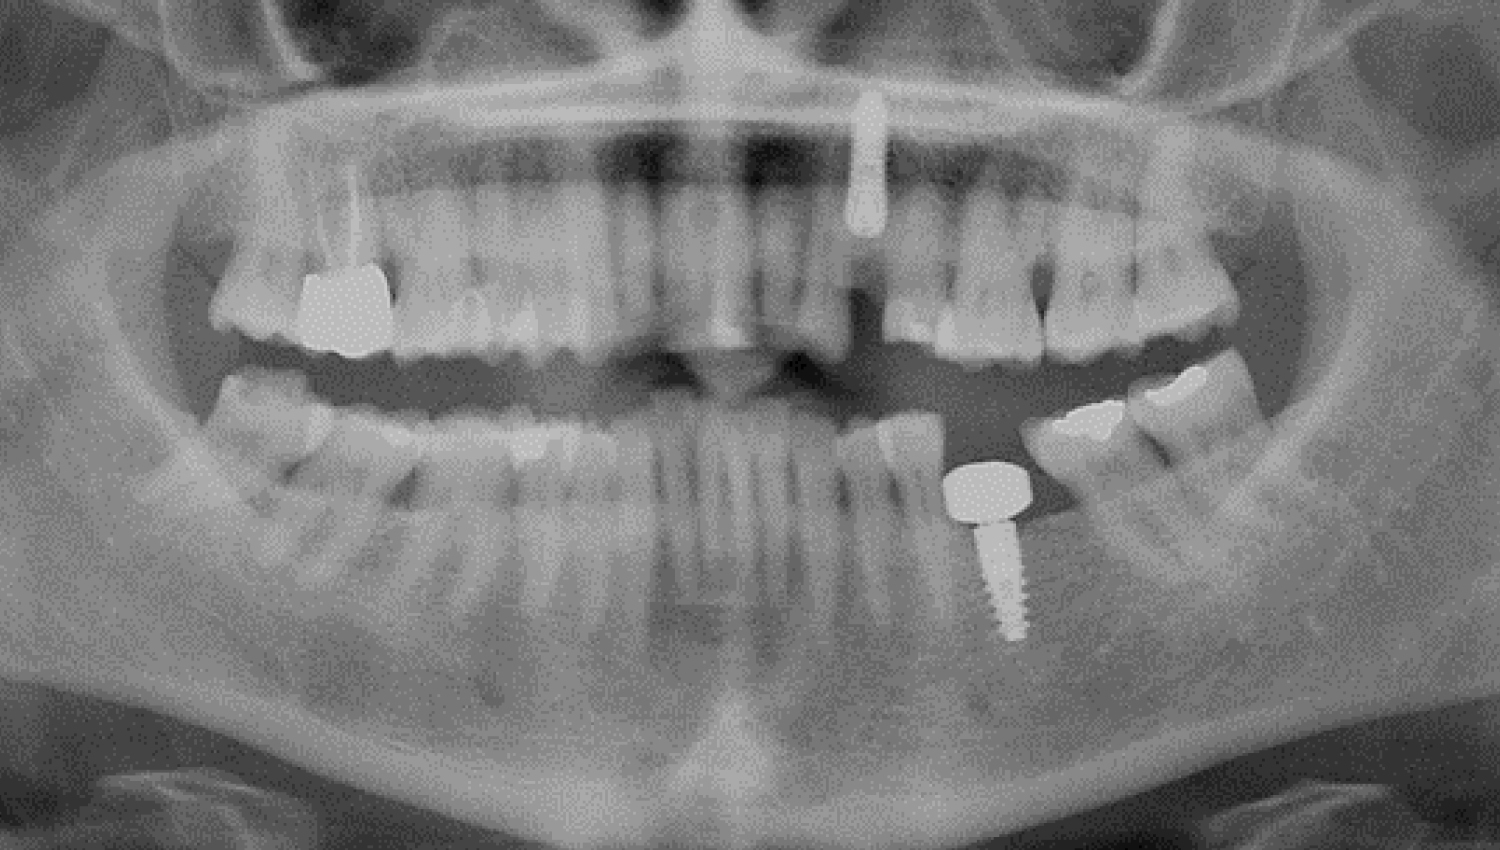

5.Final radiological view.